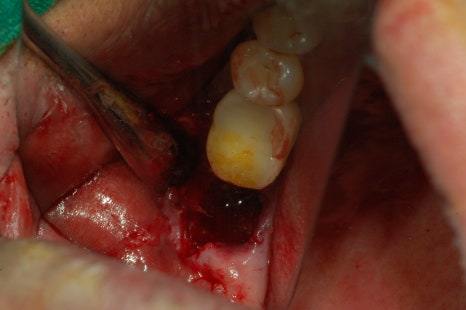

임플란트 픽스쳐가 이식이 삐뚫지 않아야 오래 사용 할 수 있습니다. 위 사진과 같이 뼈가 부족할 시에는 임플란트를 식립 후 뼈이식을 동시에 하는 경우도 생깁니다.

그 과정은 보통 치아를 뽑고나서 치아뽑은 자리에 뼈이식을 하거나 임플란트 심는 부분이 부족한 부분에 뼈이식을 진행하곤 합니다.

뼈이식 해야 할 자리를 확인 후 뼈이식을 하게 됩니다. 뼈이식을 한 후 그대로 나두게 되면 뼈가 제대로 안착이 될 수 없기 떄문에 뼈이식 한 곳 위에 멤브레인이라는 것을 얹혀놓고 실밥을 꿰매게 되는 과정을 거치고 있습니다.